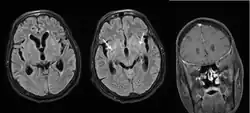

Cryptococcal meningitis

Cryptococcal meningitis (infection of the meninges, the tissue covering the brain) is believed to result from dissemination of the fungus from either an observed or unappreciated pulmonary infection. Often there is also silent dissemination throughout the brain when meningitis is present. People with defects in their cell-mediated immunity, for example, people with AIDS, are especially susceptible to disseminated cryptococcosis. Cryptococcosis is often fatal, even if treated. It is estimated that the three-month case-fatality rate is 9% in high-income regions, 55% in low/middle-income regions, and 70% in sub-Saharan Africa. As of 2009 there were globally approximately 958,000 annual cases and 625,000 deaths within three months after infection.[27]